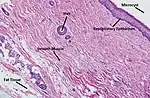

Histopathology

In case an ovarian cyst is surgically removed, a more definite diagnosis can be made by histopathology:

| Type | Subtype | Typical microscopy findings | Image |

|---|---|---|---|

| Functional cyst | Follicular cyst |

|

.jpg.webp) |

| Corpus luteum cyst |

|

| |

| Cystadenoma | Serous cystadenoma | Cyst lining consisting of a simple epithelium, whose cells may be either:[21]

|

|

| Mucinous cystadenoma | Lined by a mucinous epithelium |  | |

| Dermoid cyst | Well-differentiated components from at least two germ layers (ectoderm, mesoderm and/or endoderm).[22] |  | |

| Endometriosis | At least two of the following three criteria:[23]

|

| |

| Borderline tumor | Atypical epithelial proliferation without stromal invasion.[24] |  | |

| Ovarian cancer | Many different types, but generally severe dysplasia/atypia and invasion. | ||

| Simple squamous cyst | Simple squamous epithelium and not conforming to diagnoses above (a diagnosis of exclusion) |  | |